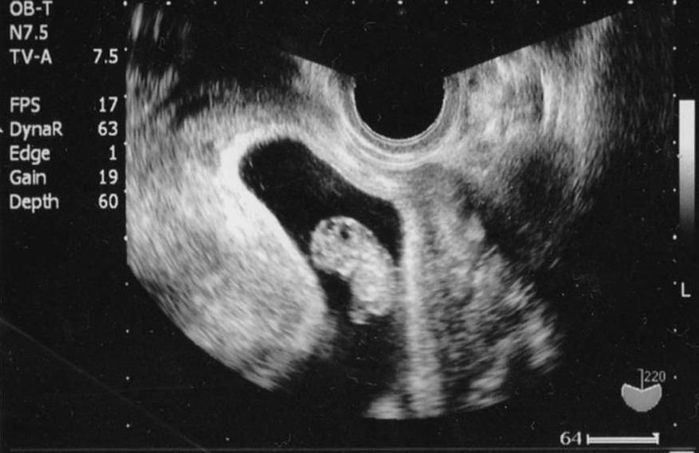

妊娠10週目のエコー写真

足が出来ました

へその緒が見えます。まだお腹に余裕があり動き回るころ。